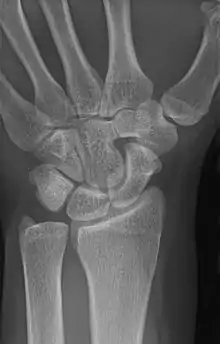

An example of a coalition between the trapezoid and capitate carpal bones

The lunate and triquetral bones are the most common carpal bones to fuse together, resulting in a lunotriquetral coalition in 1% of people. 60% of patients with a lunotriquetral coalition will have it bilaterally.[1] Among isolated incidents the capitate and hamate bones are the next most common to fuse followed by the pisiform-triquetrum, trapezium-trapezoid, scaphoid-capitate, and triquetrum-hamate.[3]